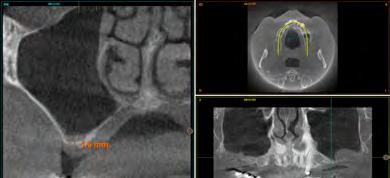

maxilares, lo que apunta a la existencia de una atrofia vertical ósea excesiva en esta área que pretende ser rehabilitada con implantes dentales (Figura 5). A mayor aumento vemos la fractura radicular de la pieza 13 que ha generado el defecto circunferencial (Figura 6) y en el cone beam de planificación se constata y además se pone de manifiesto la dimensión del defecto óseo y el volumen óseo residual a nivel palatino de 2 mm (Figura 7).

En el estudio pormenorizado del cone beam superior se constata la extrema atrofia ósea vertical en ambos sectores posteriores del maxilar que hace necesaria la elevación de seno bilateral, por abordaje convencional (Figura 8 y 9). En el seno izquierdo, el abordaje debe ser mayor al necesitar un injerto de mayor volumen (desde la zona de premolares hasta molares) por lo que la ventana de acceso de mayor longitud se conserva en Endoret-PRGF durante la cirugía para ser utilizada posteriormente como membrana ósea. En el seno del primer cuadrante, la elevación se lleva a cabo para el área molar en exclusiva. La ventana de acceso al seno maxilar izquierdo se coloca en vestibular del defecto generado tras la exodoncia de la pieza dental 13,

Figura 5. Radiografía inicial del paciente. En ella observamos el defecto crateriforme del diente 13 y una neumatización excesiva de ambos senos maxilares en el maxilar posterior donde se pretenden realizar implantes dentales. Figura 6. Imagen en detalle de la pieza 13. En esta imagen cercana podemos observar una fractura vertical evidente en el área del ápice ya en este tipo de prueba radiológica. Figura 7. En el cone-beam de planificación se objetiva la fractura y el defecto crateriforme con pérdida de la tabla vestibular completa y un remanente óseo a nivel palatino de 2 mm para la posterior inserción de un nuevo implante.